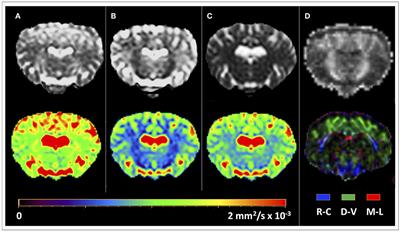

Frontiers In Vivo Diffusion Tensor Magnetic Resonance